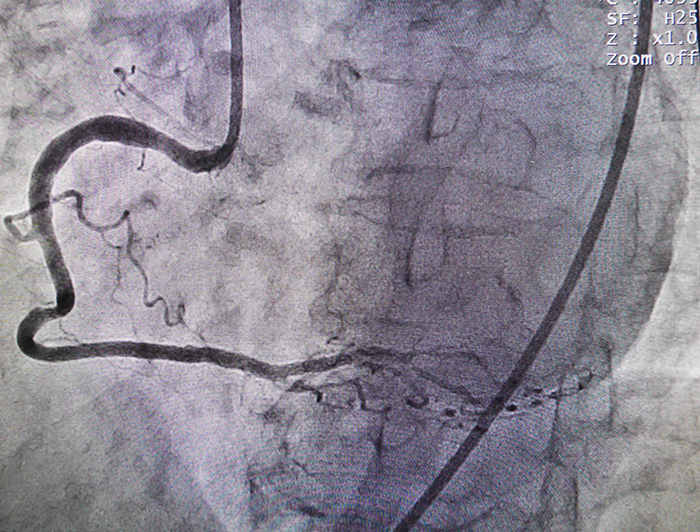

angiogram

LSU Health New Orleans interventional cardiologist Murtuza Ali, MD, led a team that performed the first coronary angioplasty using the investigational HeartMate PHP™ in Louisiana on Tuesday, December 20, 2106, at University Medical Center New Orleans. The procedure was part of the SHIELD II clinical trial to compare St. Jude Medical’s PHP (Percutaneous Heart Pump) Heartmate™ device to Abiomed’s Impella® 2.5 device for mechanical circulatory support in high-risk patients undergoing percutaneous coronary intervention (PCI), also known as coronary angioplasty.

According to the National Institutes of Health, doctors perform PCI to open coronary arteries that are narrowed or blocked by the buildup of atherosclerotic plaque. PCI may be used to relieve symptoms of coronary heart disease or to reduce heart damage during or after a heart attack.